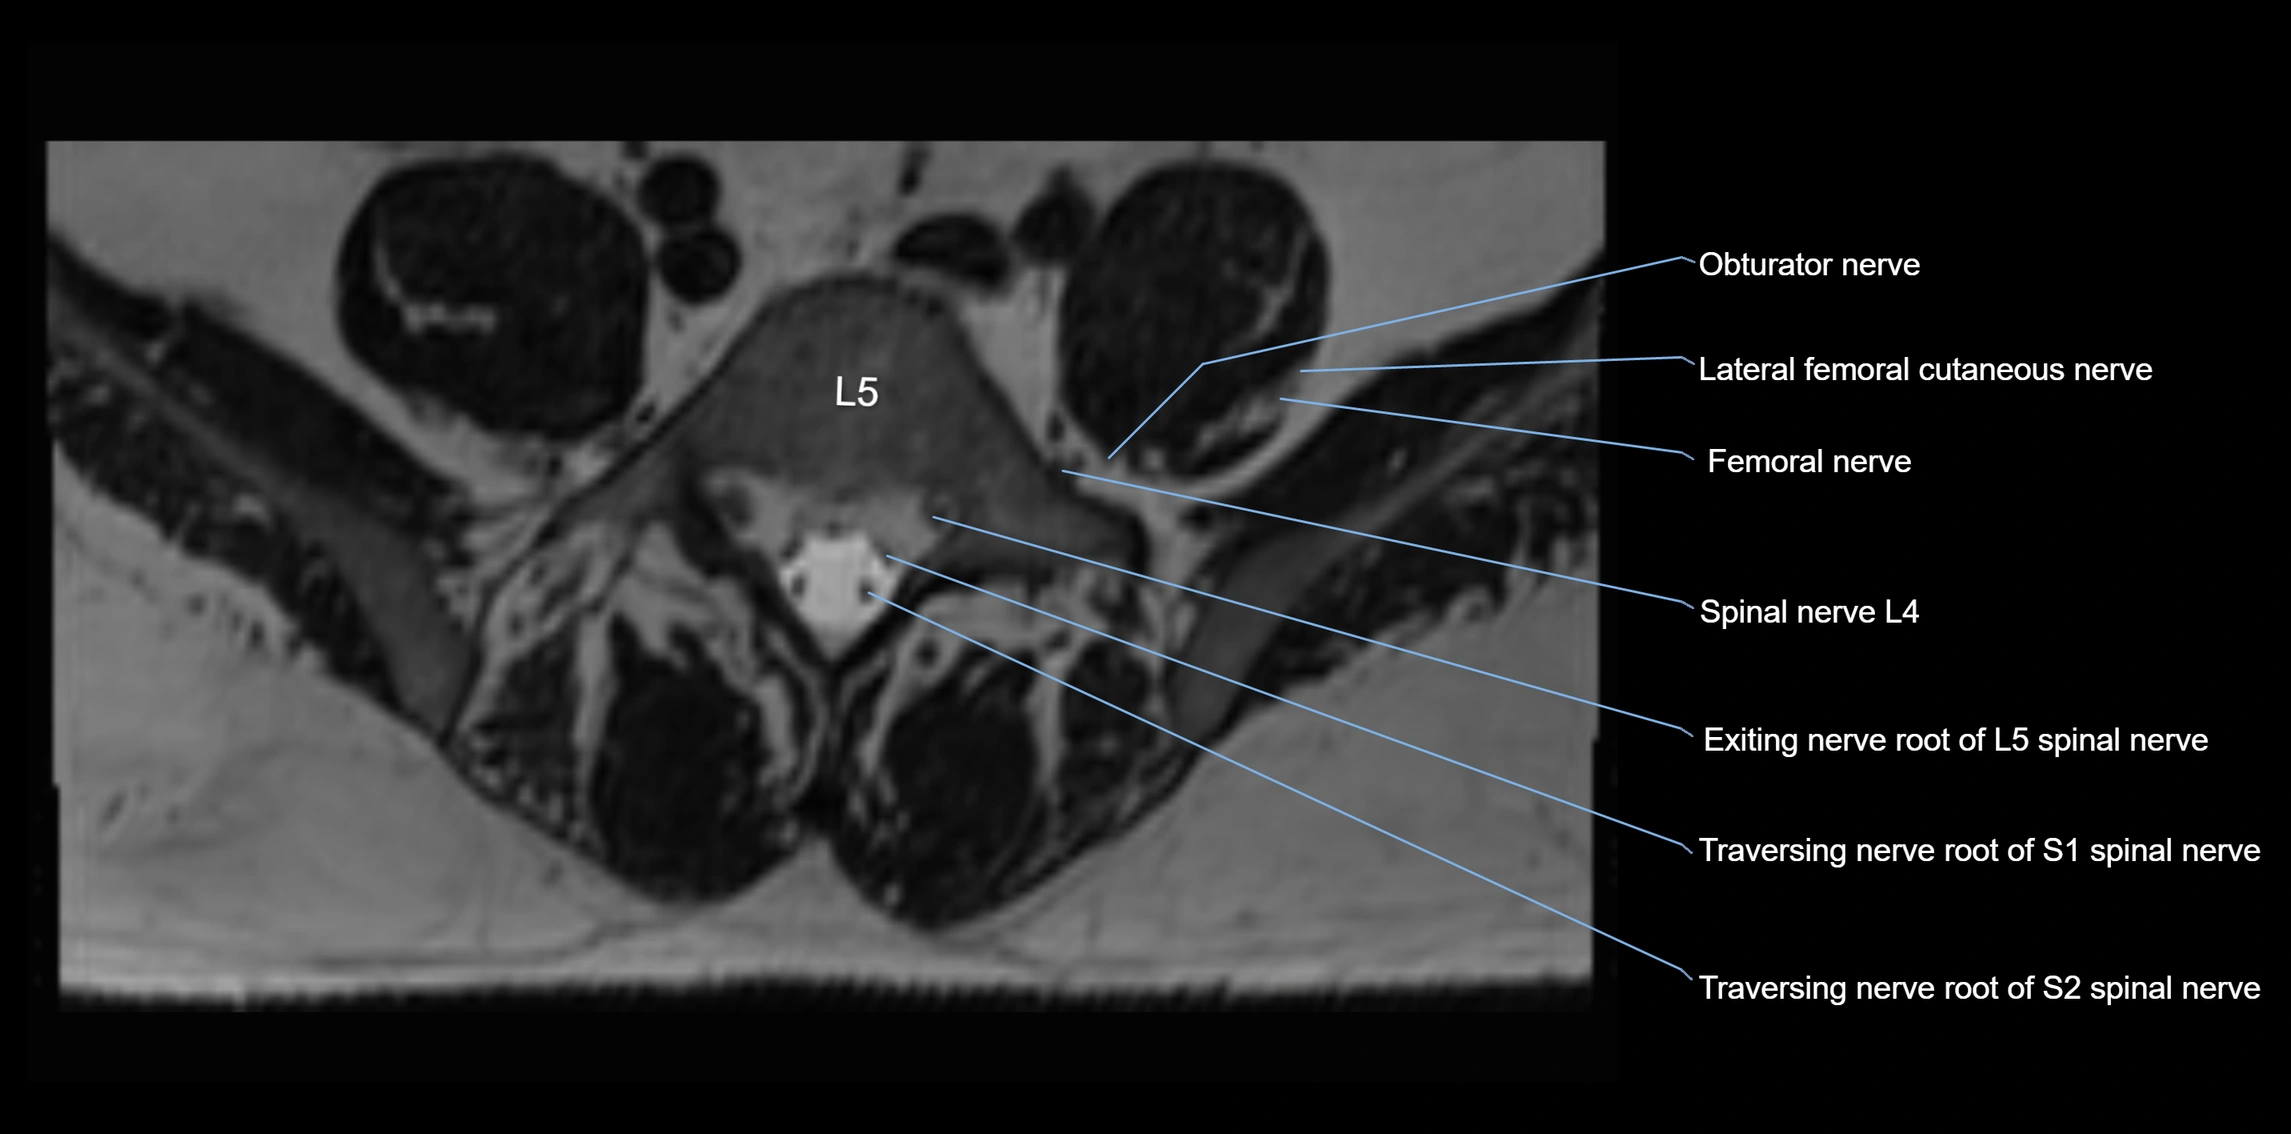

MRI image

image